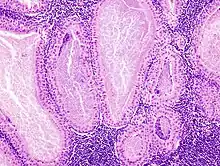

The appearance of this tumor under the microscope is unique. There are cystic spaces surrounded by two uniform rows of epithelial cells with centrally placed pyknotic nuclei. The cystic spaces have epithelium referred to as papillary infoldings that protrude into them. Additionally, the epithelium has lymphoid stroma with germinal center formation.